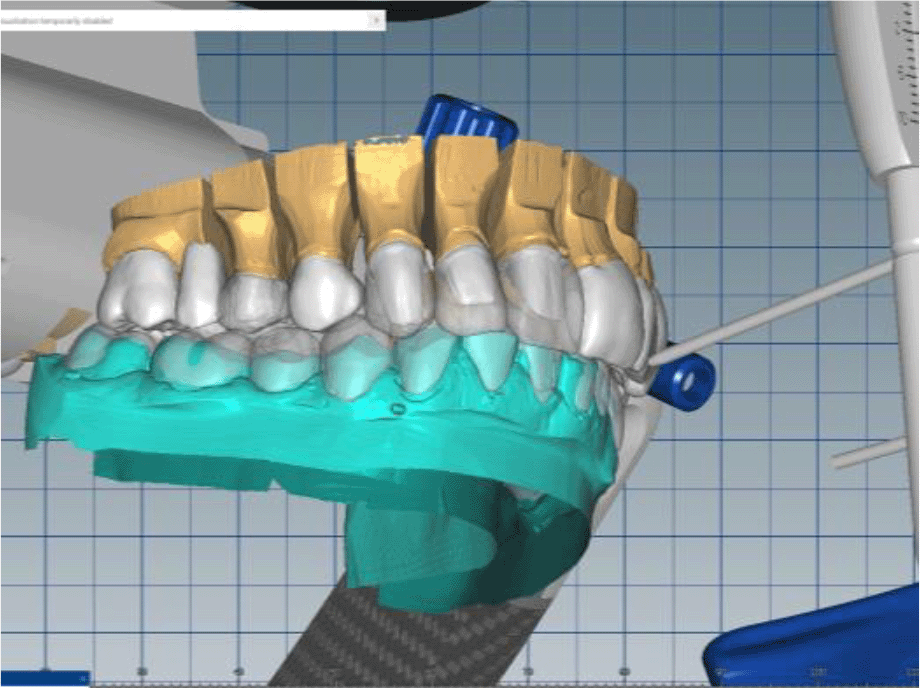

The cast gypsum models were scanned with a laboratory scanner and the obtained digital models were subjected to additional processing. Briefly, transfer of the morphological planning for the upper dentition (crown strategy) and for the lower dentition (digital wax up strategy, pontics) was performed (Figures 9 and 10).

26dd931c-41d3-478d-bec1-8cb211d0a4b8_figure9.gif

Figure 9. Clinical situation after upper preparation with increased VDO.

26dd931c-41d3-478d-bec1-8cb211d0a4b8_figure10.gif

Figure 10. Digital design on both jaws.